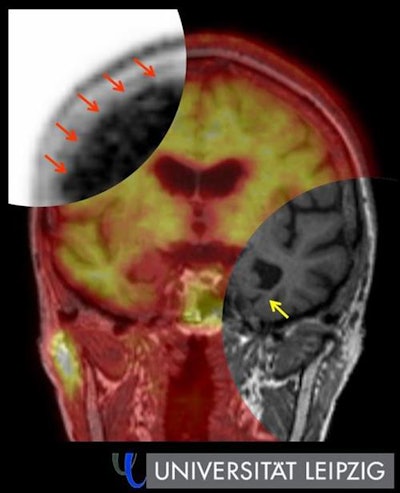

Hybrid amyloid PET/MRI in Alzheimer's disease. Top left: Evidence of amyloid plaques in the cerebral cortex (red arrow) using PET. Bottom right: Signs of hippocampus shrinkage (yellow arrow) with simultaneous MRI. Image courtesy of Leipzig University.Traditional FDG-PET reveals glucose uptake and thus the tissue's energy metabolism, while amyloid PET, which has been the subject of extensive research for some time now, is more helpful in dementia diagnosis because it reveals the amyloid protein deposited in the brains of Alzheimer's patients. "This allows us to see the disease years before brain volume starts to decrease and to better distinguish Alzheimer's from other forms of dementia."

Barthel said the future lies in a hybrid of PET and MRI. "Combined imaging using both techniques gives us a detailed picture of the anatomical and functional aspects of dementia. It's particularly suitable for routine clinical use because patients only have to visit once and we get all the key data we need from the examination."